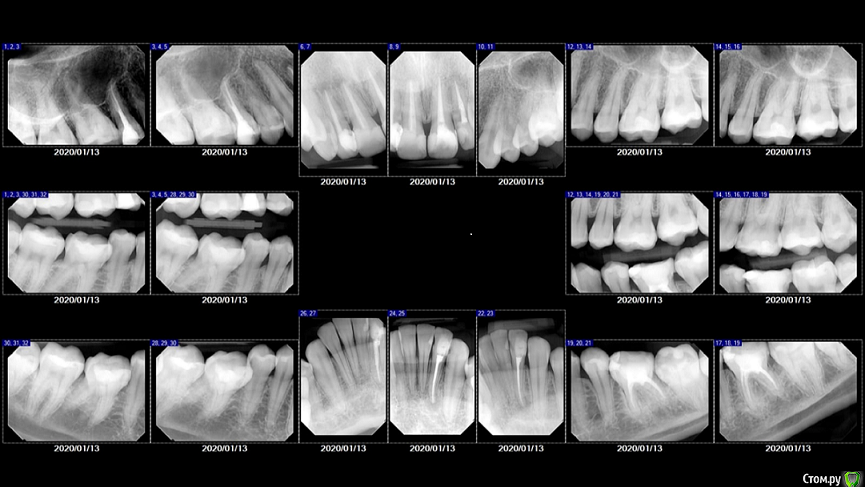

Svettala Опубликовано 18 февраля, 2020 Автор Поделиться Опубликовано 18 февраля, 2020 Добрый день, извините за задержку, но только сегодня получила снимки. Не сочтите за труд еще раз посмотреть передние зубы и высказать свое мнение ( для нас оно важно)- насколько необходимы коронки на передних зубах, может пока просто переделать пломбы для более эстетического вида и вообще, нужны ли где-либо коронки по данному снимку. Спасибо огромное. Ссылка на комментарий

kramer Опубликовано 18 февраля, 2020 Поделиться Опубликовано 18 февраля, 2020 Нужны отдельные коронки (например, emax), пломбы переделывать смысла нет. 1 Ссылка на комментарий

kramer Опубликовано 18 февраля, 2020 Поделиться Опубликовано 18 февраля, 2020 + зубы 11, 12 предварительно перелечивать каналы 1 Ссылка на комментарий

red_butler Опубликовано 19 февраля, 2020 Поделиться Опубликовано 19 февраля, 2020 Нужны отдельные коронки (например, emax), пломбы переделывать смысла нет. + зубы 11, 12 предварительно перелечивать каналы+ 1 Ссылка на комментарий

Svettala Опубликовано 20 февраля, 2020 Автор Поделиться Опубликовано 20 февраля, 2020 Нужны отдельные коронки (например, emax), пломбы переделывать смысла нет.Добрый день, возник такой еще вопрос: нам предлагают сделать здесь единую конструкцию из четырех коронок, с целью равномерного распределения давления(?) на зубы. В итоге пришли к соглашению, что будут делать две конструкции на 11,12 + 21,22. Такой вариант приемлем в нашей ситуации или все таки отдельные 4 коронки делать? Время пока есть и поэтому хочется максимально знать все нюансы, так как делается на долгое время, да и сумма приличная выходит. Ссылка на комментарий

red_butler Опубликовано 20 февраля, 2020 Поделиться Опубликовано 20 февраля, 2020 или все таки отдельные 4 коронки делать? отдельные Ссылка на комментарий